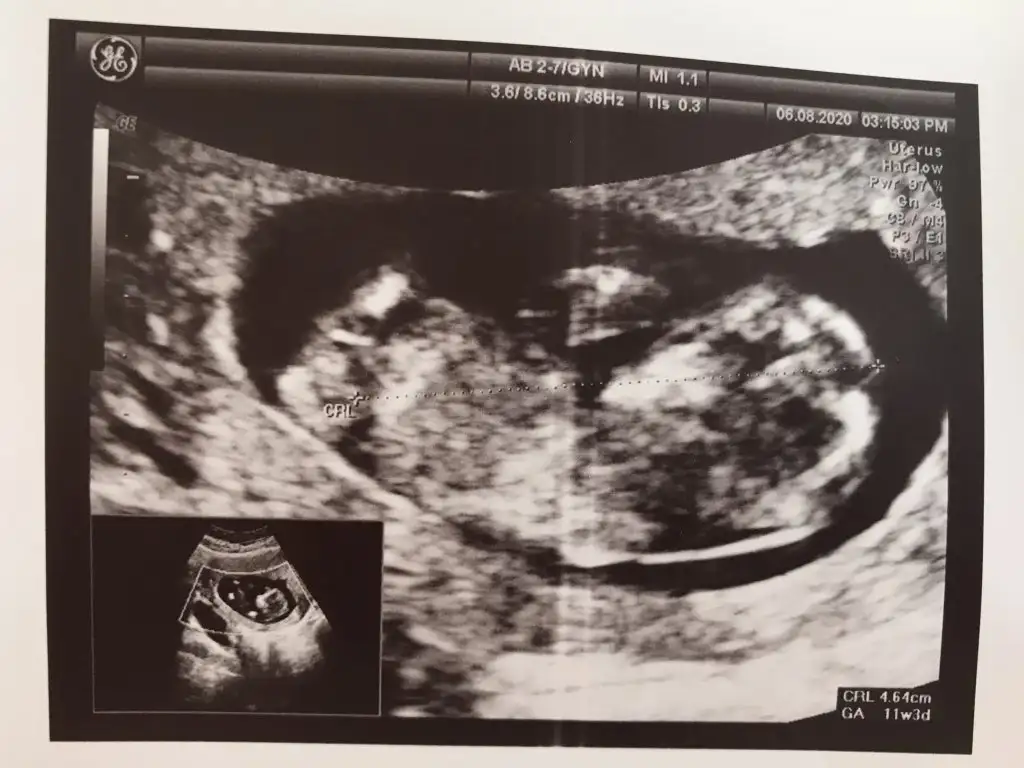

Erkek gibi başka usgde paylaşın teyit edeyim 11 12 13 haftalar olmalı USG kaç haftalıkTahmin varmi kızlar Eki Görüntüle 2671896

12+2 cnmErkek gibi başka usgde paylaşın teyit edeyim 11 12 13 haftalar olmalı USG kaç haftalık

Başka USG varmı renklide nub görünmüyor diğerinde nub çok karışık net değil